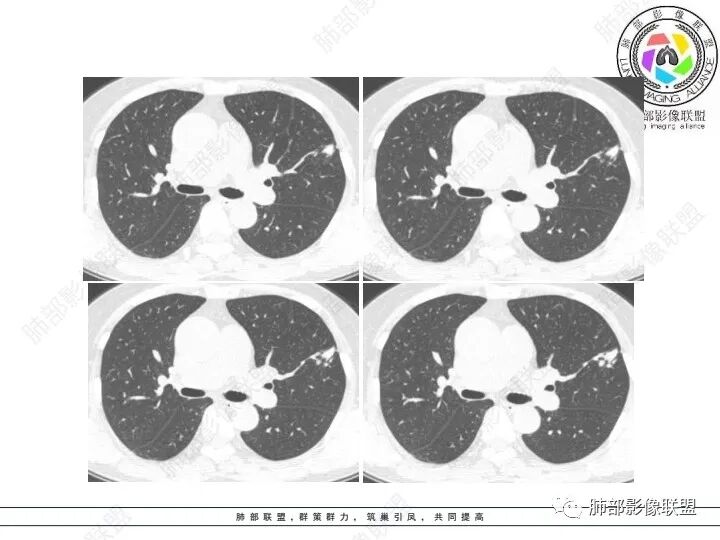

1、临床特点:61岁女性,体检发现肺结节。

2、影像特点:左肺上叶不规则病灶,冠状位、矢状位、斜状位重建显示病 灶整体沿着支气管方向呈斑片状,多结节堆积感明显,病灶大部分边缘显示平直,局部边缘稍膨隆,边界显示比较清楚,近端支气管壁显示增厚,周围可见长索条影及多发结节影,未显示典型“树芽征”。邻近叶间裂未受牵拉凹陷。纵隔窗显示病灶中央可见点状高密度钙化影。

3、病例小结:老年女性体检发现肺部结节,缺乏临床表现,需要警惕恶性。结合影像特点,左肺上叶病灶整体缺乏膨隆感,边缘大多平直,周围多发卫星灶(可见多发长索条影、并非肺CA的细短毛刺),病灶收缩力很弱(邻近叶间裂未见明显凹陷),观察1mm重建图亦可以发现病灶周围没有边界清楚的GGO,病灶内可见钙化点,肺门纵隔未见肿大淋巴结。综合以上,此病灶首先考虑炎性,结核可能性大,有条件可以增强扫描,有助于我们进一步判断。